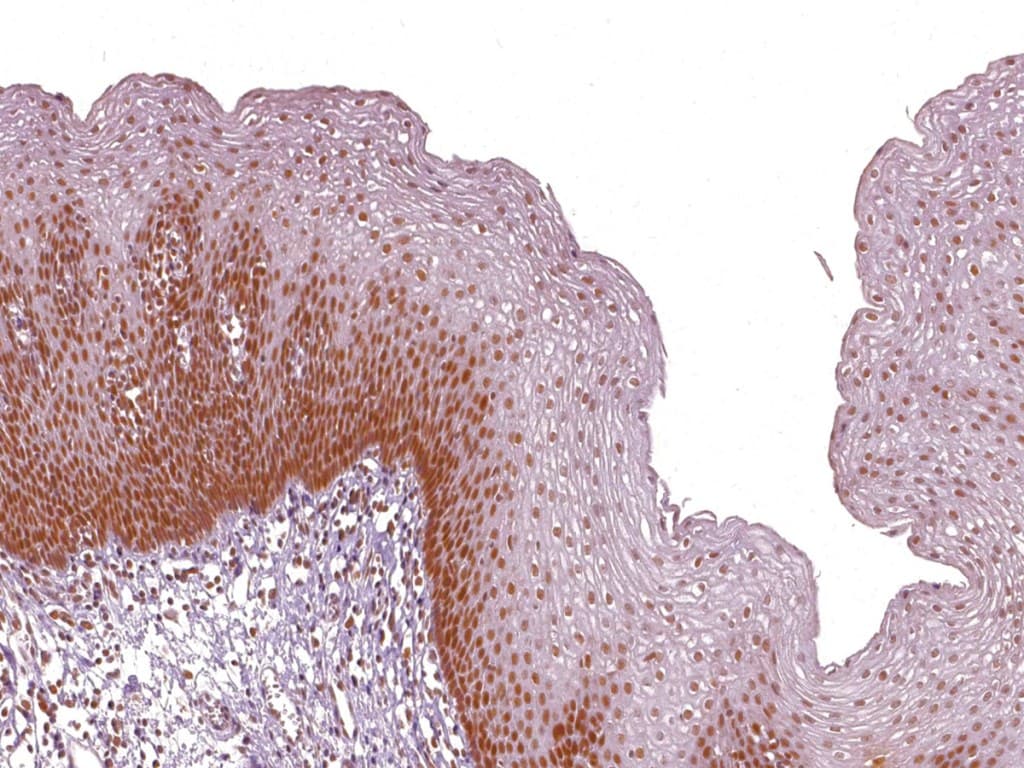

La inmunohistoquímica (IHC) de MSH2 es un método establecido para evaluar el estado de MMR. La pérdida de tinción nuclear en las células tumorales, con expresión preservada en las células estromales e inmunitarias, indica la inactivación de MSH2. La IHC complementa las pruebas moleculares de MSI y respalda la identificación del síndrome de Lynch, orientando las pruebas de línea germinal y el manejo del paciente. Los paneles de cribado universal que evalúan MLH1, PMS2, MSH2 y MSH6 permiten distinguir entre tumores esporádicos y hereditarios. En el cáncer colorrectal, la IHC de MSH2 correlaciona fuertemente con el estado MSI-H, ofreciendo una herramienta diagnóstica fiable y reproducible.

- Detección nuclear específica de MSH2, que permite una diferenciación clara entre la retención y la pérdida en las células tumorales.